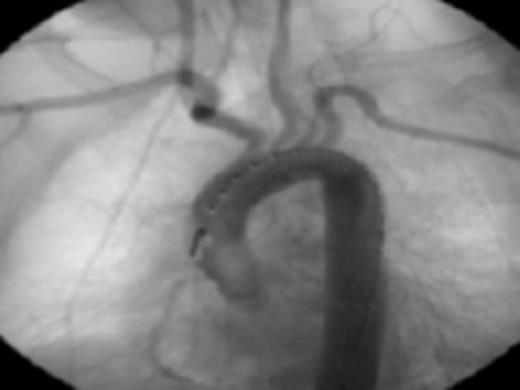

Diagnostic aortic angiography demonstrating darkening distal to the left subclavian possibly representing plaque. Image prior to stent deployment

Her past medical history of considerable GI bleeds and her significant fall risk made her a poor candidate for continued anti-coagulation therapy. The appropriateness of the lesion involved and her risk for further embolic events guided selection of endovascular technique for treatment. Exclusion was performed by a 26mm × 10cm thoracic aortic stent graft with balloon angioplasty. Post-procedure angiography confirmed position of the graft distal to the origins of the great vessels and did not demonstrate any leaks. Subsequently, she progressed well and was discharged in stable condition on warfarin and clopidogrel.